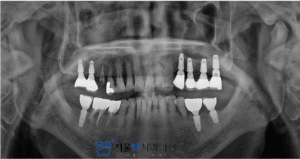

성공적으로 임플란트 식립이 된 모습입니다!

가양역치과, 서울맥치과의

섬세한 치료로 이제 편안하게 식사를

하실 수 있다고 말씀주셨어요♥

저희 서울맥치과도 불편하셨던

편측저작에서 양측으로 식사를 골고루

하실 수 있다고 하셔서 보람을 느꼈습니다.

환자분의 경우,

임플란트 보철물이 많으신 상태셨는데요.

간혹, 임플란트의 편안함으로

주기적인 검진을 놓치시기도 하는데요.

이로인해 임플란트 치주염이 발생하여

흔들리거나 주변치아에도 영향을 미칠 수 있으니